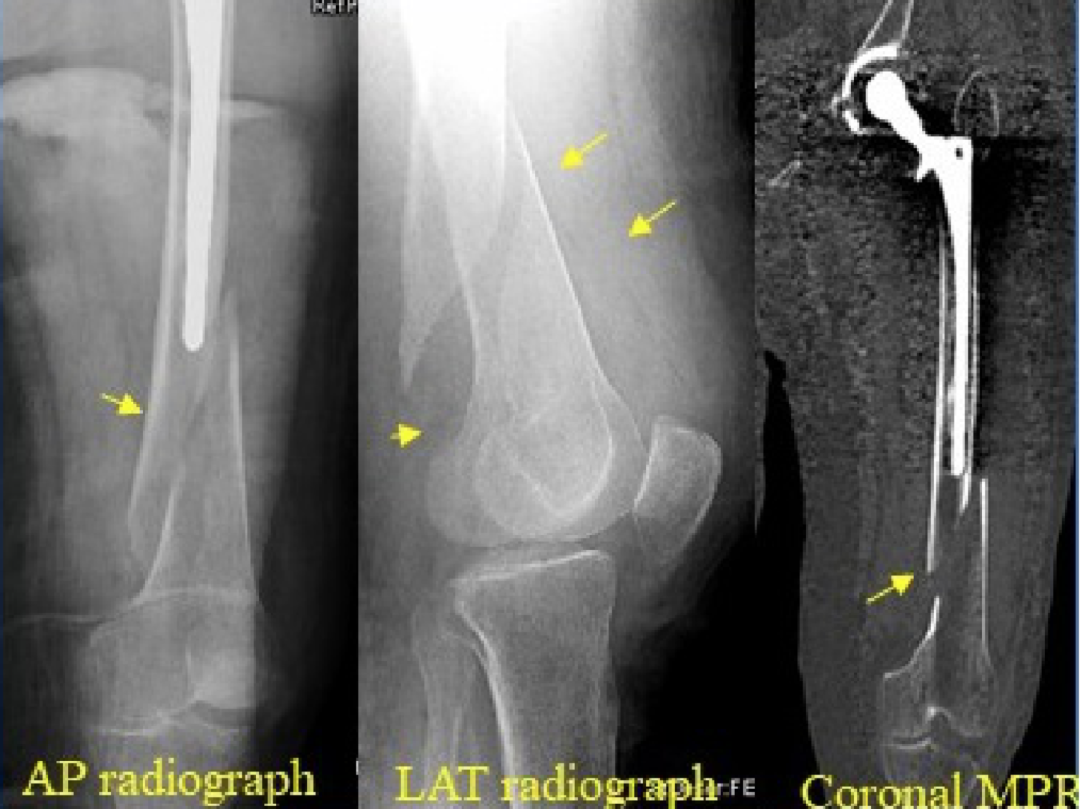

6. 假体周围骨折:

发病率 1%~2%。可发生在书中或术后。迟发性骨折多发生于股骨假体尖端。非骨水泥假体植入和翻修术更容易发生术中骨折。